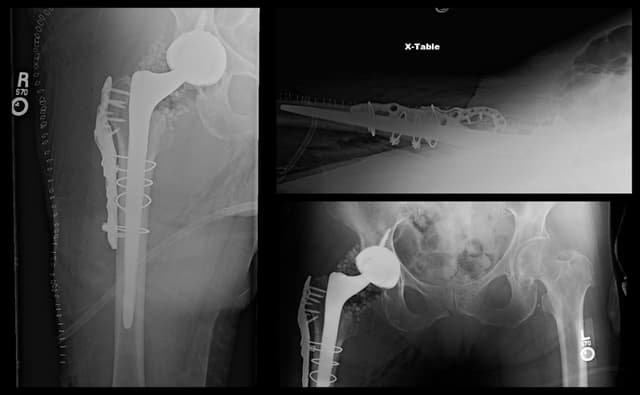

Post-op